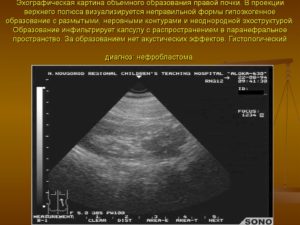

Объемное образование почки: что это, виды и лечение